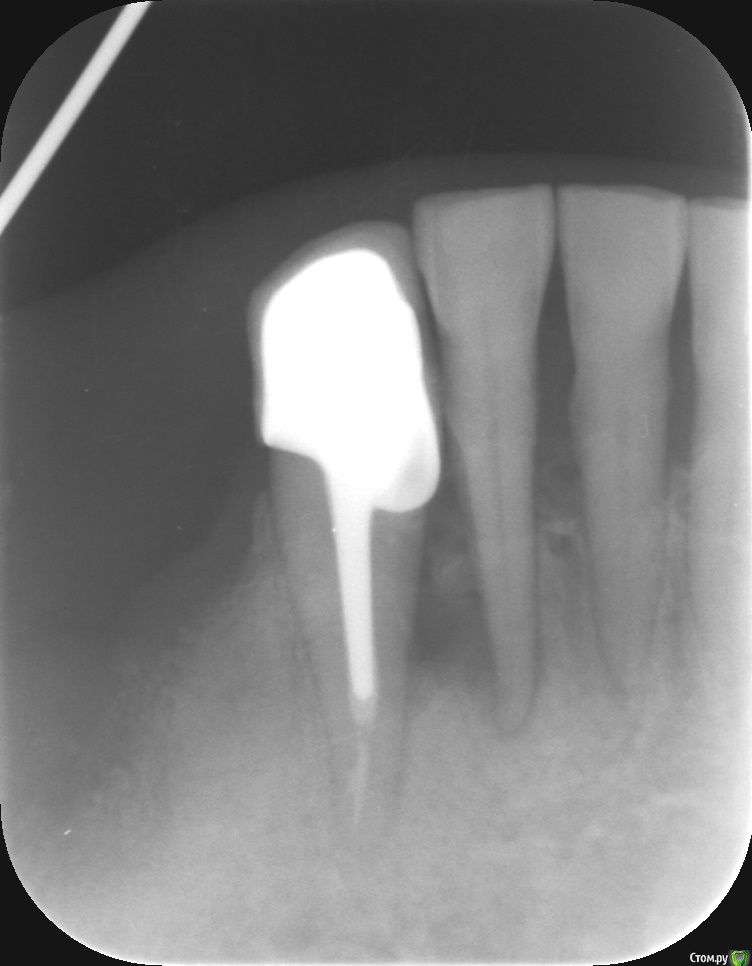

jsvc Опубликовано 17 апреля, 2017 Поделиться Опубликовано 17 апреля, 2017 Здравствуйте. подскажите пожалуйста. На очередном осмотре стоматолог сказал имеется воспаление между 42 и 43. Надо удалять 42.Предыстория такова: год назад перелечен 43 и поставлена вкладка+коронка как опора под бюгельный протез.Что-то не согласен с удалением. Мне кажется что причина воспаления в 43 (произошел скол стенки корня + нависающая коронка).Можно ли как-нибудь вылечить данную ситуацию и сохранить 42 и 43? Ни 43 ни 42 не болят.Заранее спасибо за ответ.Приолжение: панорамный февраль 2016 (качество правда никакое)прицельный март 2017 Ссылка на комментарий

jsvc Опубликовано 18 апреля, 2017 Автор Поделиться Опубликовано 18 апреля, 2017 (изменено) Я конечно не стоматолог, но как мне кажется прицельный снимок однозначно указывает на то что источником воспаления является 43 (см. форму очага воспаления во вложении).А увеличенная периодонтальная щель у 42 это следствие инфицирования периодонта из очага воспаления. Изменено 18 апреля, 2017 пользователем jsvc Ссылка на комментарий